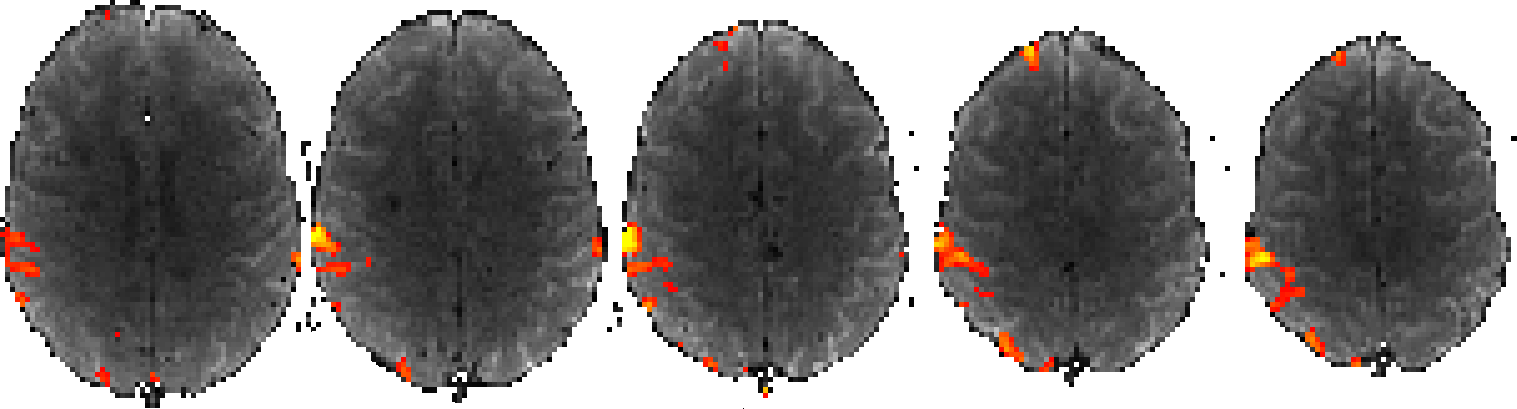

Remember that we are actually performing this process on the data for every single voxel in our dataset. This means that we will end up with an entire 3D image of t-statistics and another 3D image of p-values. We often present the results of an fMRI analysis with images that look like this:

What we are looking at here are a handful of 2D slices of our 3D dataset, with the fMRI data (averaged across time) shown in the background in grey, and the t-statistic values shown through red (low) to yellow (high). We are only displaying t-statistics that were statistically significant, i.e. all of the voxels where the t-statistic (and the corresponding p-value) was too low are not displayed.

The Post-stats page contains the good stuff - the results of the statistical analysis. Each image displays the fMRI data in the background in grey, and t-statistics in red-yellow, for the statistically significant voxels (voxels where there was no significant activation are not coloured).